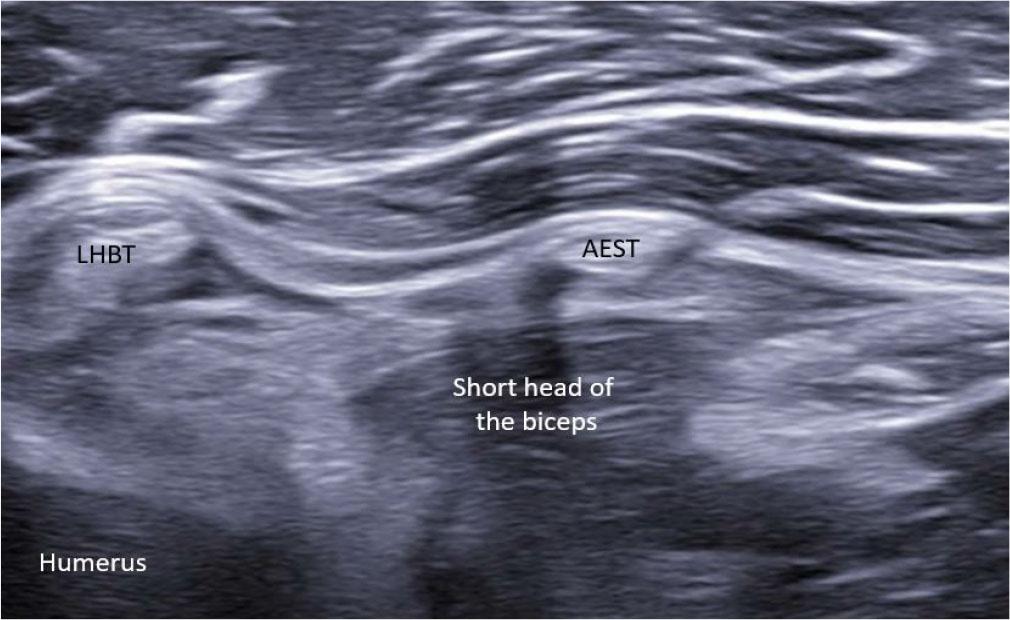

Ultrasound image showing normal aponeurotic expansion of supraspinatus tendon (AEST) anterolateral to the long head of the biceps tendon (LHBT) at the intertubercular groove

At the level of the rotator interval, AEST was assessed for echogenicity, intrasubstance tears, and its relationship to the LHBT and subscapularis tendon (Fig. 3), while the supraspinatus was checked for tear-related changes. AEST was then examined at the intertubercular groove to determine its position (intragroove, subluxation, dislocation, medial dislocation; Fig. 4), along with LHBT and subscapularis integrity. The remaining shoulder structures, including the other rotator cuff tendons and the glenohumeral and acromioclavicular joints, were systematically reviewed. The findings are summarized in Tab. 1.